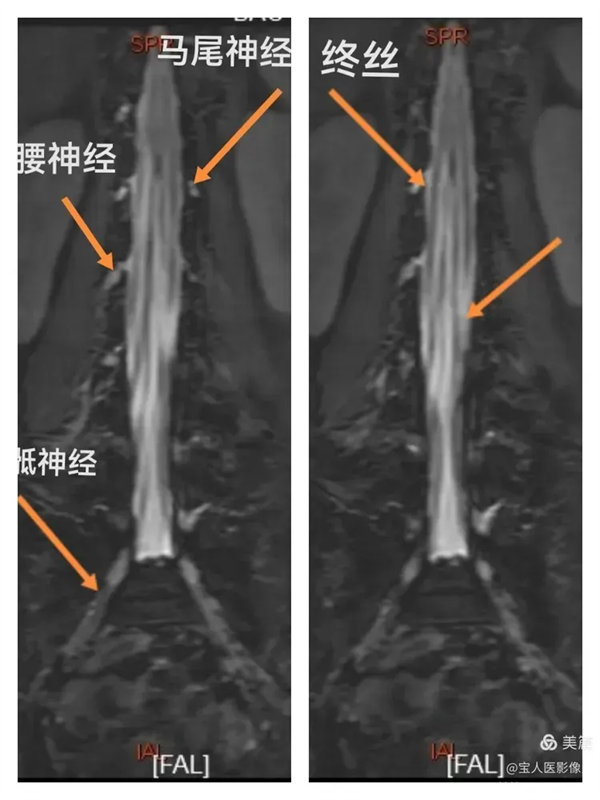

最大密度正面圖,顯示腰段硬膜囊內腦脊液(高信號),多條終絲(線狀稍低信號)縱向走行清晰。

最大密度正面圖,顯示腰段硬膜囊內腦脊液(高信號),多條終絲、腰神經及骶神經(線狀稍低信號)走行清晰。